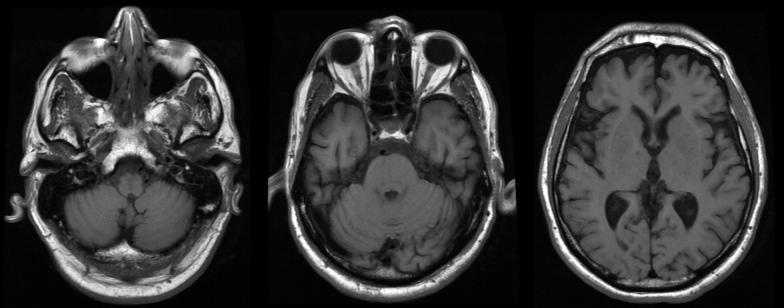

An 80-year-old man presented with dysarthria. His medical history included hypertension and dyslipidaemia. No other neurological compromise was apparent on admission. Cranioencephalic computed tomography suggested pontine and mesencephalic ischaemia and stroke treatment was implemented. Two days later, the patient displayed dysphagia that required nasogastric intubation. The next day, he developed an apparent tonic seizure with respiratory distress refractory to diazepam and phenytoin, which required sedation and invasive mechanical ventilation. Ultimately, he manifested trismus and generalized spasms. Once the diagnosis of tetanus was established, he was given anti-tetanus immunoglobulin, tetanus toxoid vaccine and metronidazole. Magnetic resonance imaging did not reveal any brain injury. During his intensive care stay, he showed cardiovascular instability, developed nosocomial pneumonia, and required prolonged ventilator support and tracheostomy. He gradually improved during a 70-day hospital stay and regained his previous functional status.

一名80岁男性因构音障碍就诊。他的病史包括高血压和血脂异常。入院时未发现其他神经功能损害。头颅计算机断层扫描提示脑桥和中脑缺血,遂实施了中风治疗。两天后,患者出现吞咽困难,需要鼻胃管插管。次日,他出现明显的强直性惊厥,伴有呼吸窘迫,地西泮和苯妥英钠治疗无效,需要镇静和有创机械通气。最终,他出现牙关紧闭和全身痉挛。破伤风诊断确立后,给他注射了破伤风抗毒素免疫球蛋白、破伤风类毒素疫苗和甲硝唑。磁共振成像未显示任何脑损伤。在重症监护期间,他出现心血管不稳定,发生医院获得性肺炎,需要长时间呼吸机支持和气管切开术。在住院70天期间,他逐渐好转,恢复到之前的功能状态。